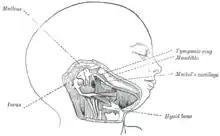

Embryologie

L'enclume se développe par processus enchondral depuis la crête neural, et dérive du 1er arc branchial. Il correspond initialement à l'extrémité du cartilage de Meckel, avant de s'en détacher pour former un os propre. Sa formation débute lors de la 16e semaine de gestation embryonnaire et se termine à la 26e semaine[3]. Comme le malleus, il pourrait avoir une moelle osseuse fonctionnelle à la naissance, mais qui invoque rapidement pour disparaitre complètement après la deuxième année de vie[4].

L'enclume est présent chez les mammifères, C'est l'homologue de l'os carré présent chez les autres vertébrés.